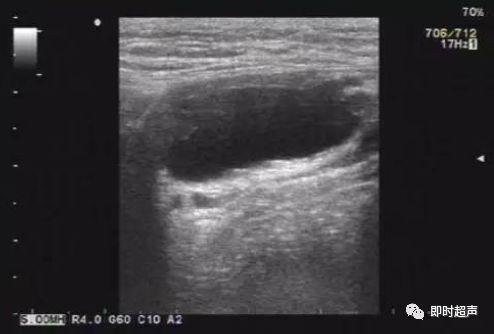

子宫圆韧带囊肿的超声诊断

右侧腹股沟囊性包块---------圆韧带囊肿?

女性腹股沟圆韧带囊肿

nuck囊肿